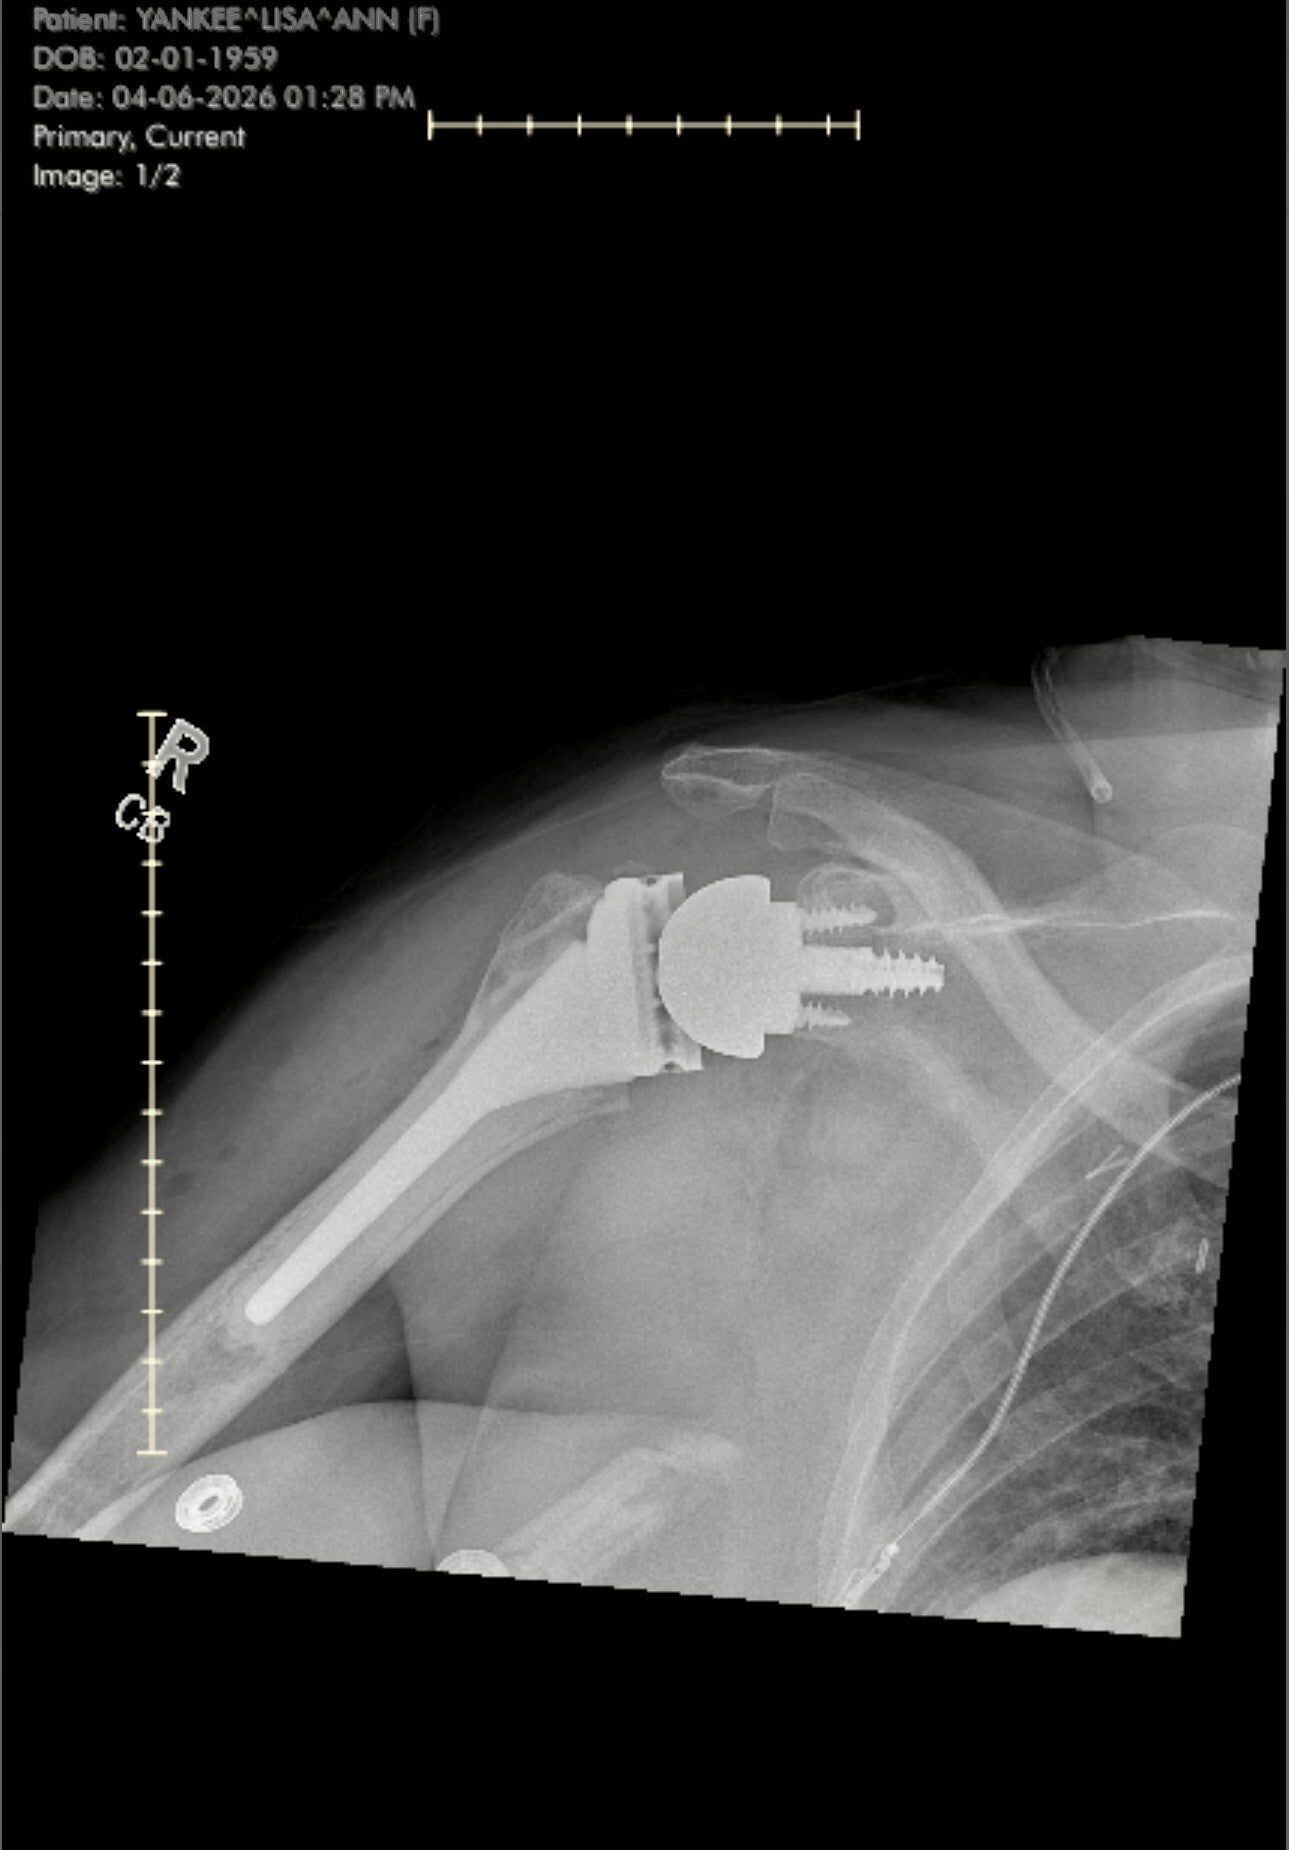

Charting the path to recovery

Welcome to the 'Recovery milestones' section of My journey through shoulder replacement. Here, I'll share the significant steps and achievements in my healing process, offering a glimpse into what to expect and how to navigate your own recovery journey.